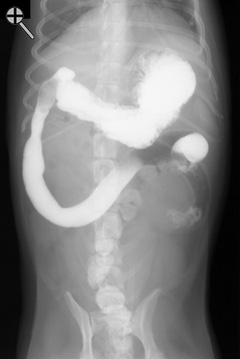

Barium was administered orally and the radiographs were taken 5 minutes later